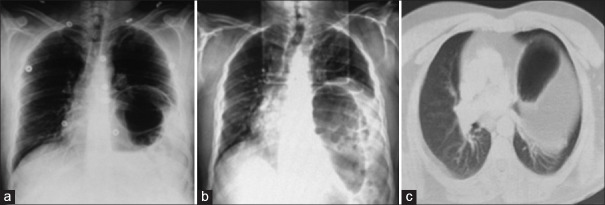

Abstract Image